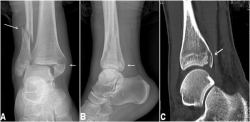

Mắt cá chân là phần xương nhô lên ở vị trí giao cẳng chân với bàn chân. Phần xương nhô lên ở mặt trong của cẳng chân gọi là mắt cá chân trong. Đó thực ra không phải là một xương riêng biệt mà là phần cuối của xương xương chày hay xương ống chân.